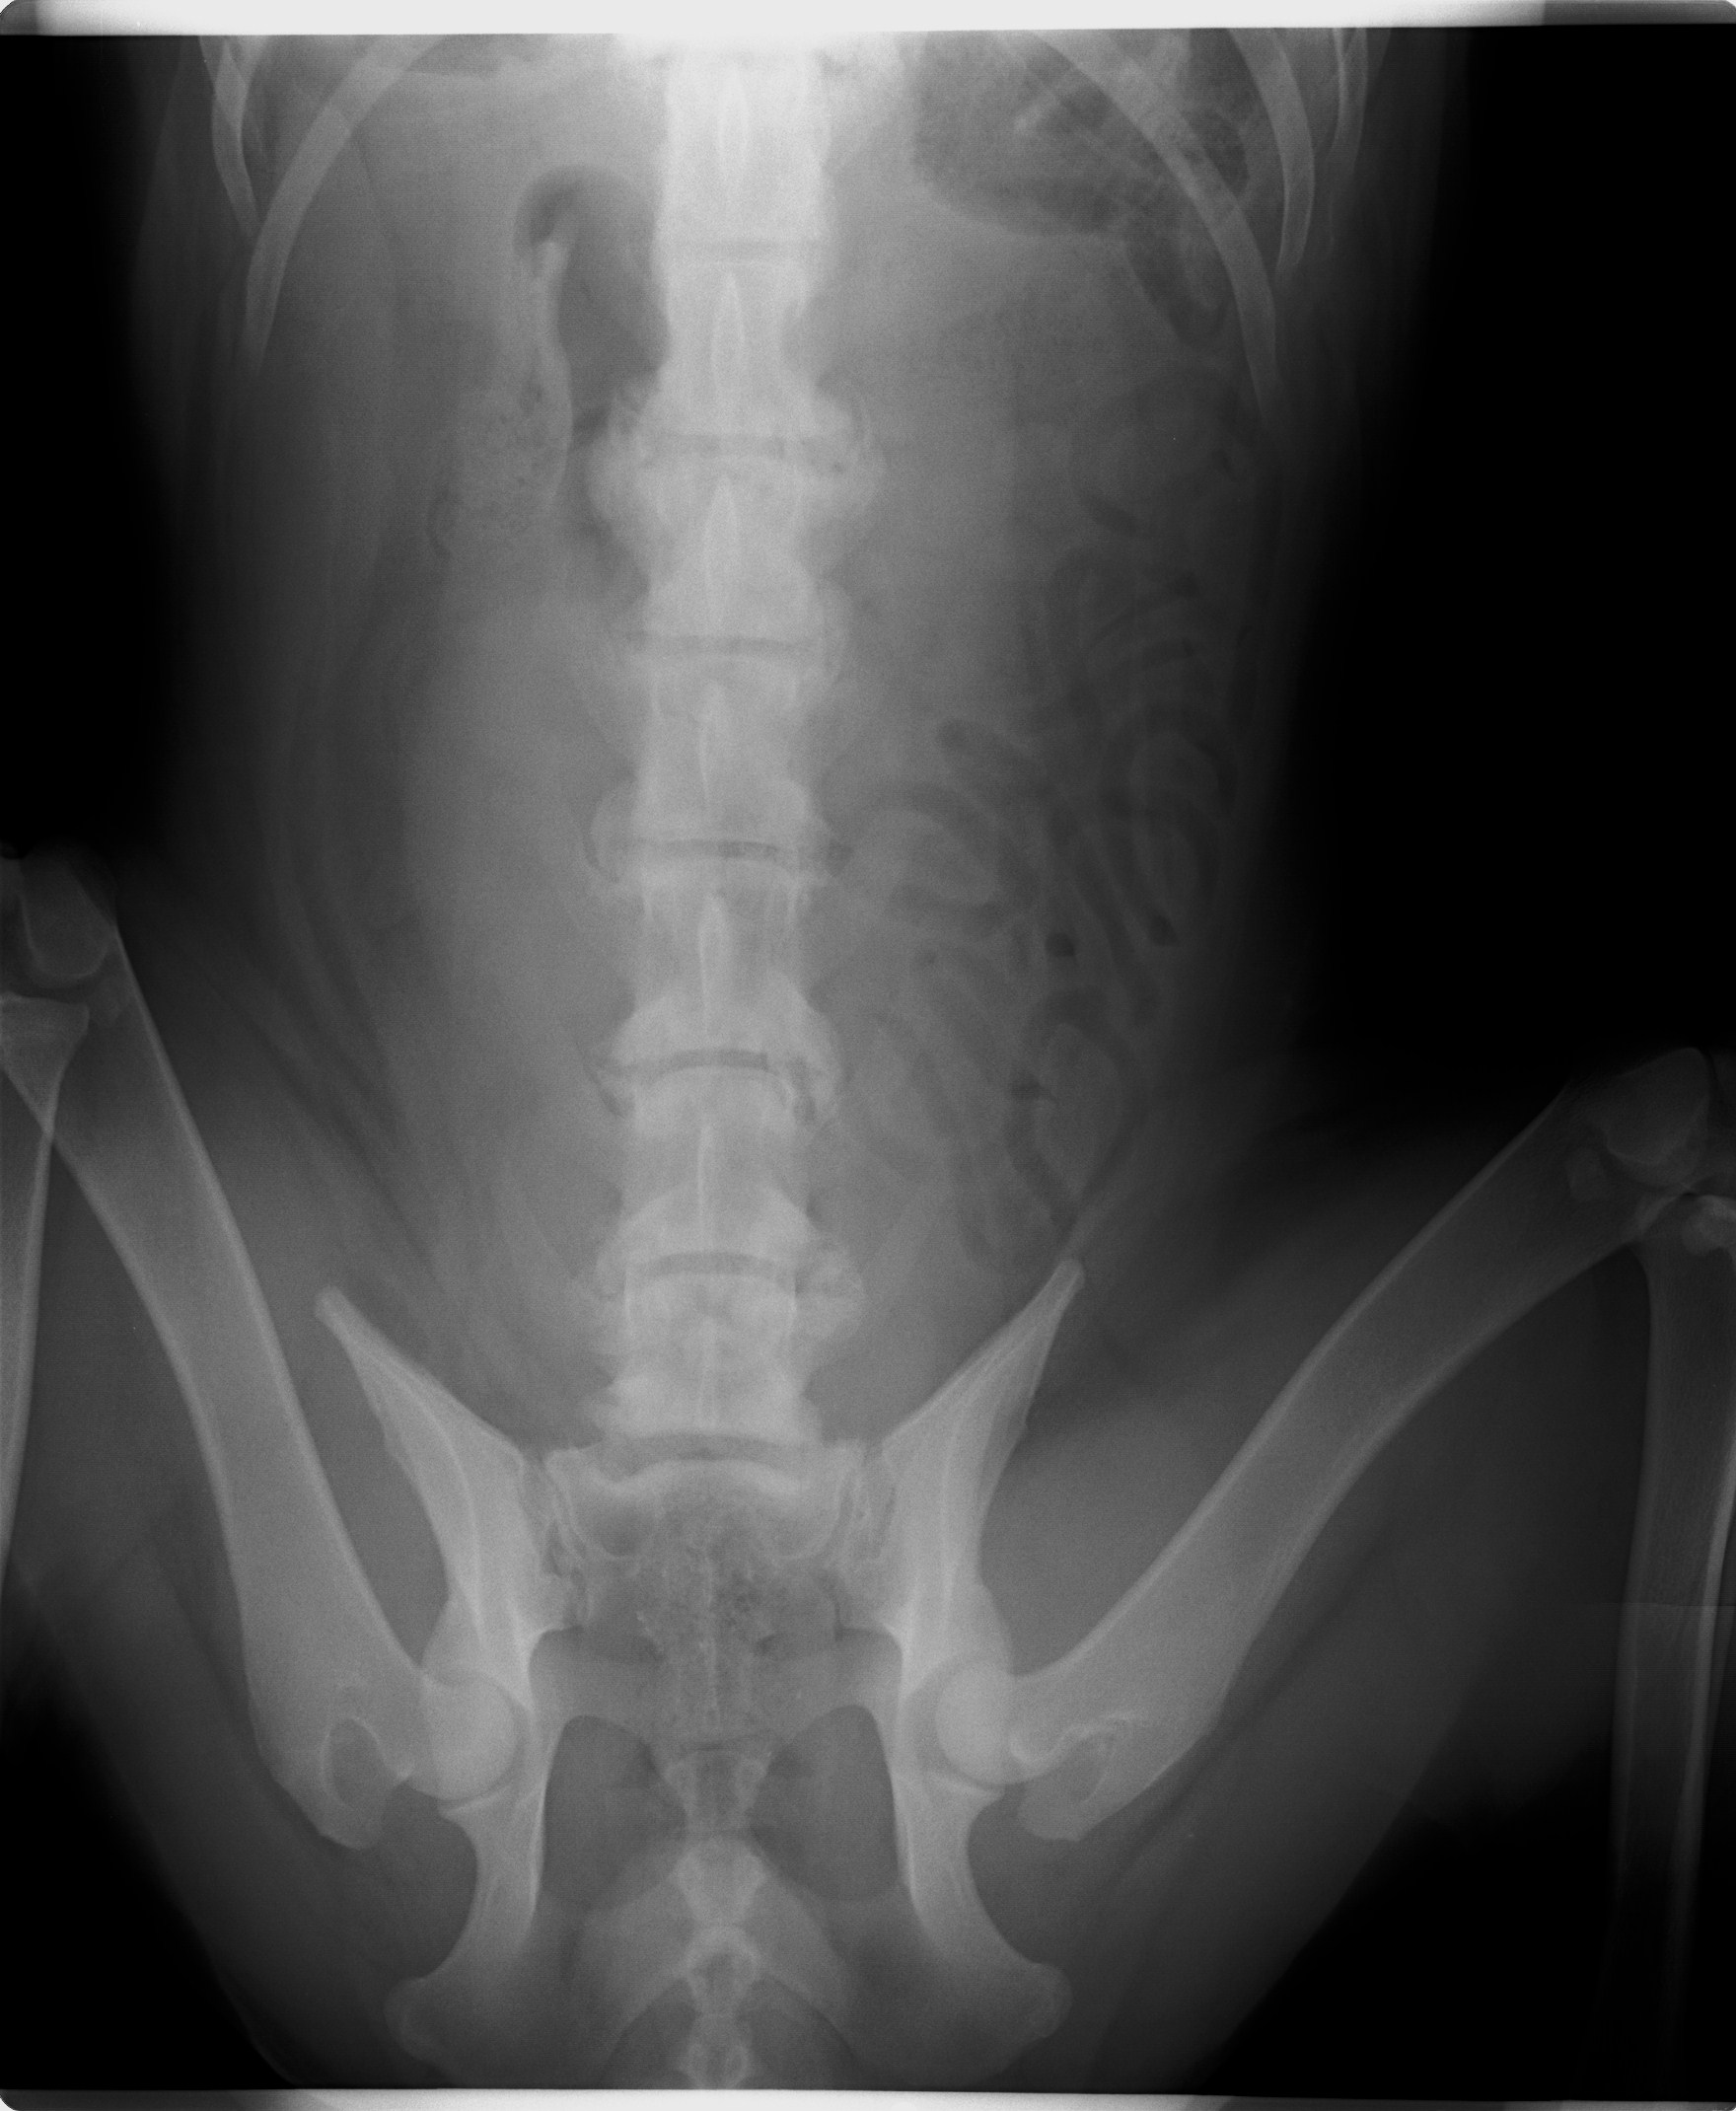

Akira, narodená cca február 2009, sa našla pri Lehniciach. V tejto lokalite je to už za posledný pol rok asi piata akita, takže je evidentné, že sa ich nejaký množiteľ zbavuje! Akira je dokonalou predstaviteľkou plemena americká akita. Má za sebou neľahké obdobie, prešla to totiž operáciou vyskočenej platničky, ktorej predchádzal život v krutých bolestiach :( Platnička je opäť na mieste, ale Akira má problém s celou chrbticou, ktorá je zrastená (prikladáme RTG snímky). Akira sa teda bude musieť doživotne šetriť, aby nemala zbytočné bolesti. To znamená kontrolovaný pohyb, určite nenechávať niekde na dvore bez dozoru, aby celý deň lietala! Prechádzky iba na vodítku, kľudne na dlhom, ale treba dať pozor aby nezabehla a nezačala sa hrať na naháňačku. Skákanie minimalizovať ako sa len bude dať, a ideálne žiadne schody! Akira si túto starostlivosť ale veľmi zaslúži :) Je to neopísateľný miláčik, lásky má na rozdávanie aj za troch. Miluje ľudí, úplne každého človeka zbožňuje, aj toho, ktorého ešte nepozná :) Na klinike si ju celý personál zamiloval a ona sa túlila ku každému. Akiru nám dokonale opísal pán doktor na klinike, ktorý povedal, že "je to miláčik, ale jadrový fyzik to nie je" :D Toto Akiru dokonale vystihuje ale to samozrejme neznamená, že sa nič nedokáže naučiť, len z nej nikdy nebude komisár Rex a ani Hatchiko :D Je to také milé trdielko, ktoré nechce nič iné, ako milovať a byť milovaná. Je nenáročná, nekonfliktná, znášanlivá so psíkmi aj fenkami, jednoducho dokonalá. Hľadá si rodinu, ktorá jej bude vedieť zabezpečiť potrebnú opateru a starostlivosť. Samozrejme konzultácia novej rodiny s ortopédom je možná. Akira čaká na svoju druhú šancu od februára 2017.

Akira, geboren ca. im Februar 2009, wurde in Lehnice gefunden. In dieser Umgebung ist das schon fünfte Akita in den letzten 6 Monaten, also offensichtlich werden die von ein Vehrmehrer rausgeschmissen. Akira ist typischer Darsteller von Amerikanische Akita. Sie hat schwere Zeiten hinter sich. Sie hat große Schmerzen im Rücken gehabt, ihre Bandscheibe wurde operiert. Bandwechsel ist wieder auf seinem Platz, aber Akira hat Problem mit dem ganzen Rückgrat (die RTG Bilder legen wir bei). Akira muss sich den Rest des Lebens schonen, damit sie keine unnötigen Schmerzen hat. Das heißt die Bewegung unter Kontrolle zu halten, kein freies Laufen am Hof ohne Aufsicht. Die Spaziergänge nur an der Leine, auch auf längeren, nur man muss aufpassen dass sie nicht laufen will. Springen muss so viel es geht minimalisiert, ideal keine Treppen. Akira verdient sich diese Sorgfalt :) Sie ist ein unbeschreibliches Liebling, Liebe kann sie für drei verschenken. Sie liebt sehr alle Menschen, sogar auch Fremde :) In der Klinik hat sie das ganze Personal geliebt. Akira wurde von Hr. Doktor so beschrieben: „sie ist ein Liebling, kein Kernphysiker“ Das heißt aber nicht, dass sie nichts lernen kann, aus ihr wird nur kein Kommissar Rex und kein Hatchiko werden. Sie ist so lieb und das einzige was sie will ist geliebt zu werden und jemanden zu lieben. Sie ist nicht anspruchsvoll, konfliktlos, erträgt sich mit anderen Hunden, einfach vollkommen! Sie sucht eine Familie die ihr die notwendige Versorgung geben kann. Selbstverständlich sind weitere Konsultationen mit einem Orthopäden möglich. Akira wartet auf ihre zweite Chance seit Februar 2017.